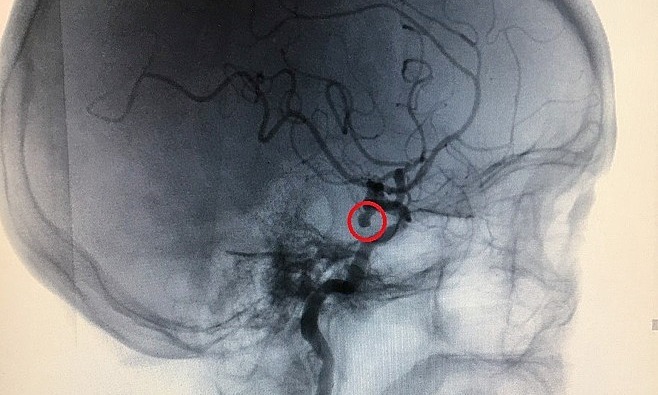

Một số yếu tố này tăng lên Nguy cơ vỡ túi phình, chẳng hạn như tuổi tác, huyết áp cao, hút thuốc lá, thành viên trong gia đình mắc chứng phình động mạch, v.v. Vỡ túi phình. Kích thước của túi phình được coi là yếu tố quan trọng nhất để xác định điều trị. – –ISUIA nghiên cứu (International Intracranial Aneurysm Rupture Study) được coi là trường hợp vỡ phình mạch lớn nhất trong não cho đến nay. 1692 bệnh nhân có túi phình từ 2 mm trở lên, trong đó có 1077 bệnh nhân có túi giãn hoàn toàn, kết quả là trong vòng 5 năm, Không Một người bị vỡ một túi phình nhỏ hơn 7 mm ở tuần hoàn trước. Xác suất vỡ túi phình động mạch chủ sau cao hơn, chiếm khoảng 1,5% trong 5 năm. Nếu túi phình khoảng 7-12mm, đặc biệt khi nó lớn hơn. Hơn 12mm, nó bị vỡ Nguy cơ sẽ tăng lên .—— Hiện tại, có 3 lựa chọn để can thiệp túi phình động mạch não không bị gián đoạn, bao gồm phẫu thuật kẹp túi phình, can thiệp đóng túi phình và điều trị bảo tồn. – Hai nghiên cứu phân tích tổng hợp đã đánh giá Kết quả của việc kẹp túi phình không bị gián đoạn, người ta thấy rằng tỷ lệ tàn tật là 4%, 1% và 10,9%, và tỷ lệ tử vong tương ứng là 1% và 2,9%. Nguy cơ tử vong do phình mạch tuần hoàn sau hoặc phình động mạch lớn. có thể lớn hơn 20%. 4%; tỷ lệ tử vong là 1 ~ 2%. Trong nghiên cứu ISUIA, tỷ lệ tử vong của nhóm can thiệp là 3,1%. Nguy cơ tử vong cũng cao hơn, có thể là túi phì đại tuần hoàn hoặc túi phình to hơn phía sau. -Điều trị bảo tồn bao gồm kiểm soát huyết áp, tránh hút thuốc và uống rượu. Điều quan trọng là theo dõi chứng phình động mạch bằng kỹ thuật chụp mạch không xâm lấn (như MRA hoặc CTA) sau 6 tháng hoặc một năm để đánh giá mức độ gia tăng kích thước khối u.- TS Thắng chỉ rõ: “Chỉ nên chọn công nghệ chụp ảnh đường trường cho các đường trượt. Nếu bạn chọn ARM lần đầu thì nên lặp lại ARM sau đó để tránh sai sót giữa 2 công nghệ này. Đối với những túi phình còn nguyên có kích thước nhỏ hơn 7mm thì đây là sự lựa chọn hợp lý.

BS Thắng khuyến cáo, khi túi phình có kích thước lớn hơn 12mm, nhất là bệnh nhân trẻ tuổi, có tiền sử gia đình thì nên điều trị ngoại khoa hoặc can thiệp nội mạch sớm. Túi phình to từ 7 đến 12 mm nên được xử lý thận trọng vì hiện tại không có bằng chứng nào cho thấy can thiệp tốt hơn điều trị bảo tồn. Kích thước túi phình của nhóm bệnh nhân này nên được theo dõi 6 tháng một lần. Quyết định bắt đầu can thiệp sớm phụ thuộc vào các yếu tố liên quan, chẳng hạn như tuổi, tiền sử gia đình, vị trí của túi phình, sự gia tăng kích thước, v.v. Hiện tại không có bằng chứng cho thấy thuốc kháng sinh được sử dụng. Sự kết tập tiểu cầu và chống đông máu làm tăng nguy cơ vỡ túi phình. Do đó, bác sĩ Tang cho rằng không nên loại bỏ những loại thuốc này. Hầu hết các trường hợp là chứng phình động mạch bảo tồn. Khuyến cáo nên sàng lọc các nhóm đối tượng có nguy cơ cao, chẳng hạn như gia đình có thành viên bị vỡ phình mạch và bệnh nhân mắc bệnh thận đa nang.